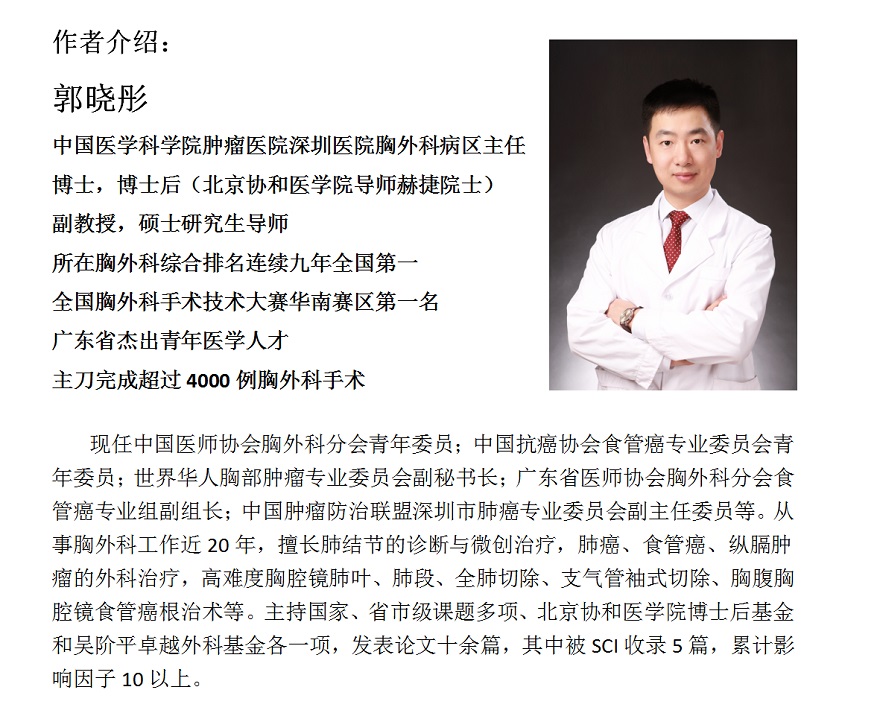

肺结节其实是医学上一类肺影像学表现的统称。其中最常见也是最重要的当属肺磨玻璃影(GGO,ground glass opacity)。GGO在胸部CT表现为密度轻度增高的云雾状淡薄影 / 圆形结节,样子像磨砂玻璃或者云朵的密度一样,所以叫磨玻璃影。(如下图红箭头所示)

图一 肺磨玻璃影